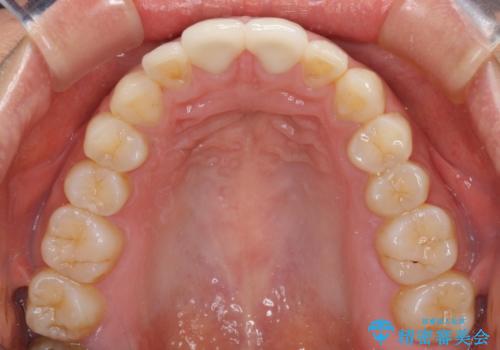

虫歯もない前歯を削ることは、処置をする者として心苦しいのですが、患者様は矯正治療は選択しないとのことだったので、オールセラミッククラウンにて補綴治療を行いました。

短期間で思い通りの仕上がりとなり、患者様には大変満足していただきました。